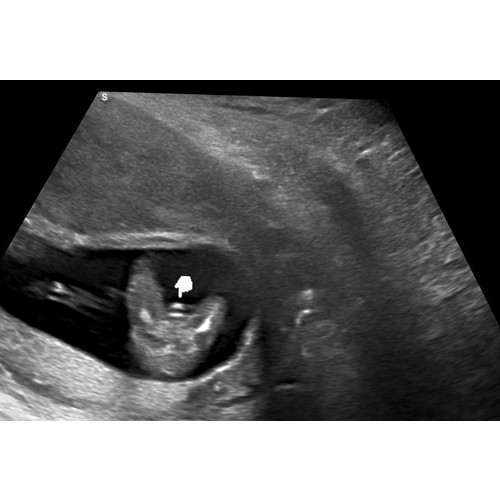

Dit is met de 20weken echo en we krijgen een jongen 💙🥰

Deze is inderdaad super duidelijk!